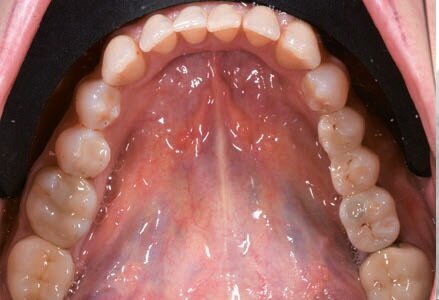

Dopo aver valutato con la paziente tutti i pro e i contro abbiamo deciso di prediligere la scelta dei REX PiezoImplant. È stata eseguita un’impronta digitale che è stata accoppiata tramite il software di progettazione all’esame radiografico tridimensionale. Sono stati scelti due impianti REX PiezoImplant 1,8 x 11. L’impronta digitale della situazione pre-intervento della paziente ci ha permesso di utilizzare quest’ultima (come ceratura diagnostica) per programmare il posizionamento implantare in modo protesicamente guidato. La pianificazione software della fase chirurgica e l’utilizzo di una guida per il corretto posizionamento dell’impianto “asse implanto- protesico”, ci hanno permesso non solo di ottenere il posizionamento implantare nel rispetto dello spessore osseo disponibile “asse anatomico” ma anche di ricercare la migliore soluzione protesica avvitata, “asse protesico”, per una sensibile riduzione del rischio di errore. È stata creata una dima chirurgica che ci ha permesso di riportare nel cavo orale la programmazione dell’inserimento implantare che avevamo pianificato virtualmente. La metodica Rex permette di utilizzare una slitta che prevede una chirurgia guidata con sistema Pilot utilizzando l’inserto W2. Sono state raccordate le due preparazioni e le abbiamo estese con l’inserto OT7S3 che ci ha permesso di ottenere una maggiore elasticità ossea.

Dopo 6 mesi abbiamo effettuato delle Rx di controllo e misurato nuovamente il valore ISQ. Dopo aver riscontrato valori positivi abbiamo svitato le viti di guarigione e abbiamo avvitato gli specifici REXmarkers direttamente sugli impianti REX PiezoImplant. Abbiamo quindi effettuato un’impronta digitale con l’ausilio di uno scanner digitale Carestream 3600. Con l’esportazione dei file STL è stato possibile realizzare una protesi avvitata disegnata con Exocad*** che dispone al suo interno delle librerie protesiche REX PiezoImplant. È stato quindi consegnato il manufatto protesico definitivo che è stato avvitato a 25 N dopo aver controllato radiograficamente il corretto accoppiamento.